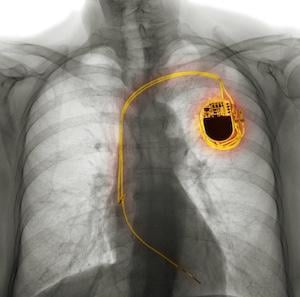

Photo: Getty Images

April 24, 2026 — A new analysis from the NOAH – AFNET 6 trial shows that artificial intelligence (AI) can help unlock data from pacemakers to better understand stroke risk in patients with device-detected atrial fibrillation (AF). The study found that patients who spent more time in AF did not have a higher risk of stroke or other cardiovascular events than those who spent less time in AF. Researchers presented these findings today as a late-breaking clinical trial at Heart Rhythm 2026.